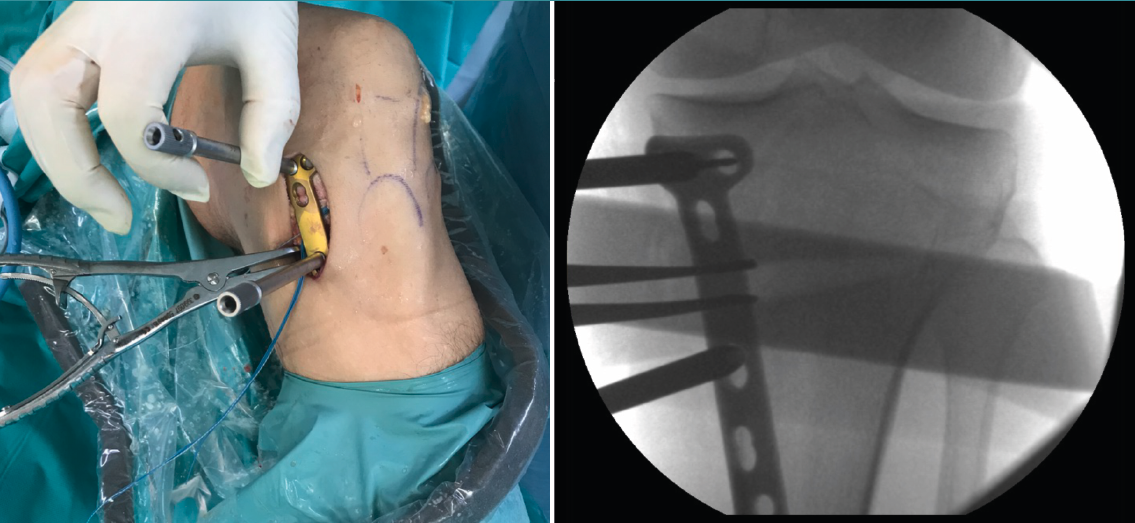

Posteriormente, bajo control radioscópico, se realiza la osteotomía apoyando la sierra por debajo de la aguja guía, llegando hasta 1 cm de la cortical lateral. Se introducen los escoplos para abrir la osteotomía (Figura 4). El primer escoplo, el más ancho, se introduce primero para comprobar el corte completo de la cortical posterior. Seguidamente, se coloca el medidor del ángulo de apertura (Figura 5A) y, a continuación, se introduce el distractor en la parte posterior de la osteotomía, evitando así un aumento de la PTP (Figura 5B). En este momento, se puede introducir en la apertura de la osteotomía el aloinjerto o sustituto óseo. Los autores utilizan aloinjerto óseo cuando la apertura es mayor de 10°. Antes de colocar y fijar la placa de osteotomía, se realiza el túnel tibial utilizando las herramientas artroscópicas clásicas (Figuras 6A y 6B). Al realizar una osteotomía biplanar, el corte es suficientemente distal como para permitir brocar el túnel tibial de la RLCA sin dificultades.

Una vez hecho el túnel tibial, se introduce la plastia y se fija a nivel femoral y tibial (Figura 7). Si se utiliza una plastia de isquiotibiales, los autores recomiendan una fijación femoral cortical de suspensión regulable, dejando unos milímetros para el ajuste final después de la colocación de la placa de osteotomía. Una vez fijada la plastia, se procede a la colocación de la placa de osteotomía TomoFix® (Synthes, Oberdorf, Switzerland) para la tibia proximal medial (Figura 8). En la mayoría de los casos el tornillo más anterior coincide con el túnel tibial de RLCA, motivo por cual no se coloca (Figura 9).

Figura 5. A: medición del ángulo de apertura de la osteotomía con el medidor; B: colocación del distractor en la parte posterior de la osteotomía, evitando así el aumento de la pendiente tibial posterior.